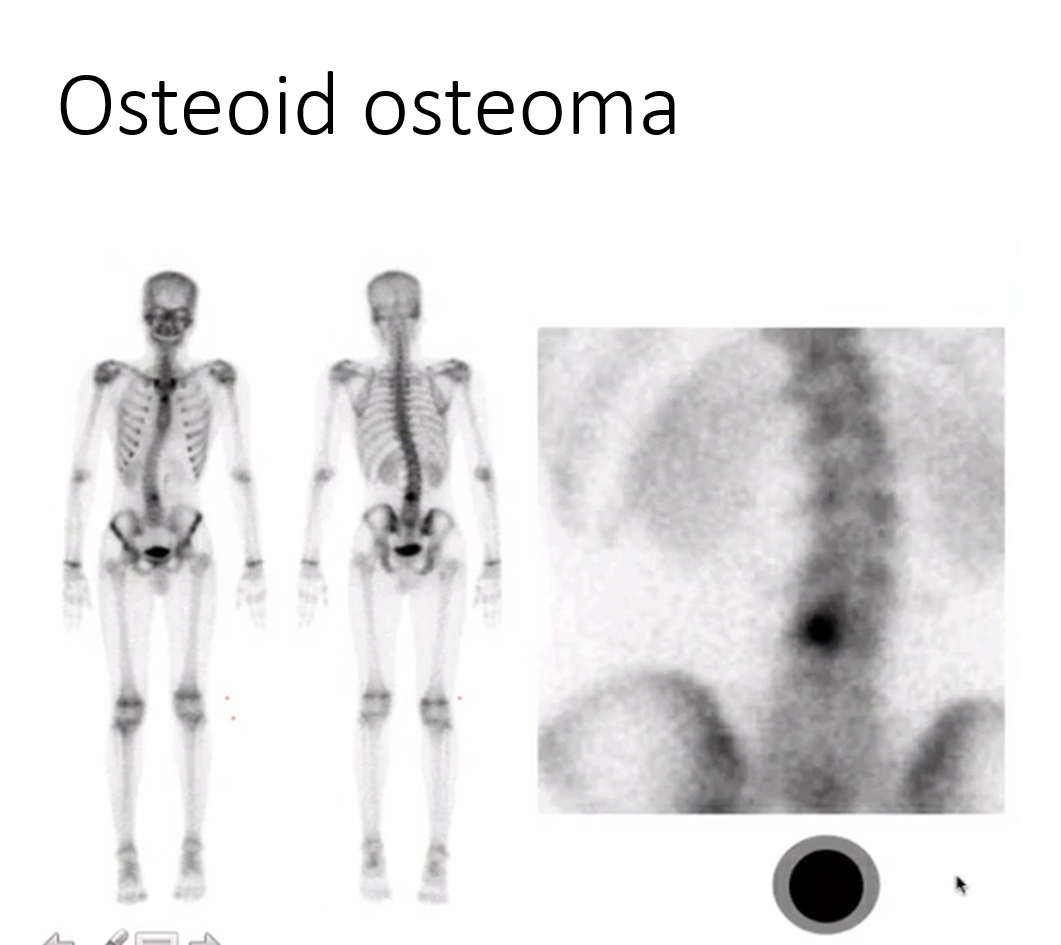

painful scoliosis

osteoid osteoma in the posterior elements